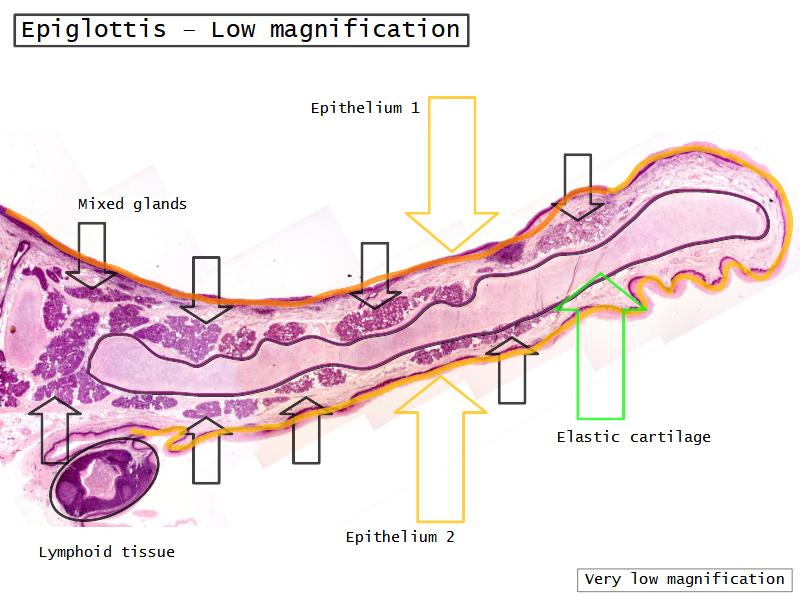

- Slide 111: Epiglottis

Epiglottis